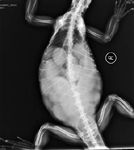

A 2-year-old intact female bearded dragon (Pogona vitticeps) was presented to Tufts University's Cummings School of Veterinary Medicine for evaluation of weakness and anorexia of one day's duration. On initial presentation, the bearded dragon was lethargic, with a distended coelom and pale mucous membranes. The results of the initial blood work revealed severe anemia; the patient's packed cell volume was 6% (reference range = 24% to 36%).1 A dorsoventral radiograph revealed multiple rounded (about 1 cm in diameter), coalescing, soft tissue opacities throughout the caudal coelomic cavity (Figure 1). Preovulatory stasis was tentatively diagnosed. Coelomic ultrasonography was recommended to evaluate the abdominal opacities, but the owner declined further investigation.

1. A dorsoventral radiograph of a bearded dragon with preovulatory stasis. Note the multiple rounded coalescing soft tissue opacities throughout the caudal half of the coelomic cavity, consistent with follicles.